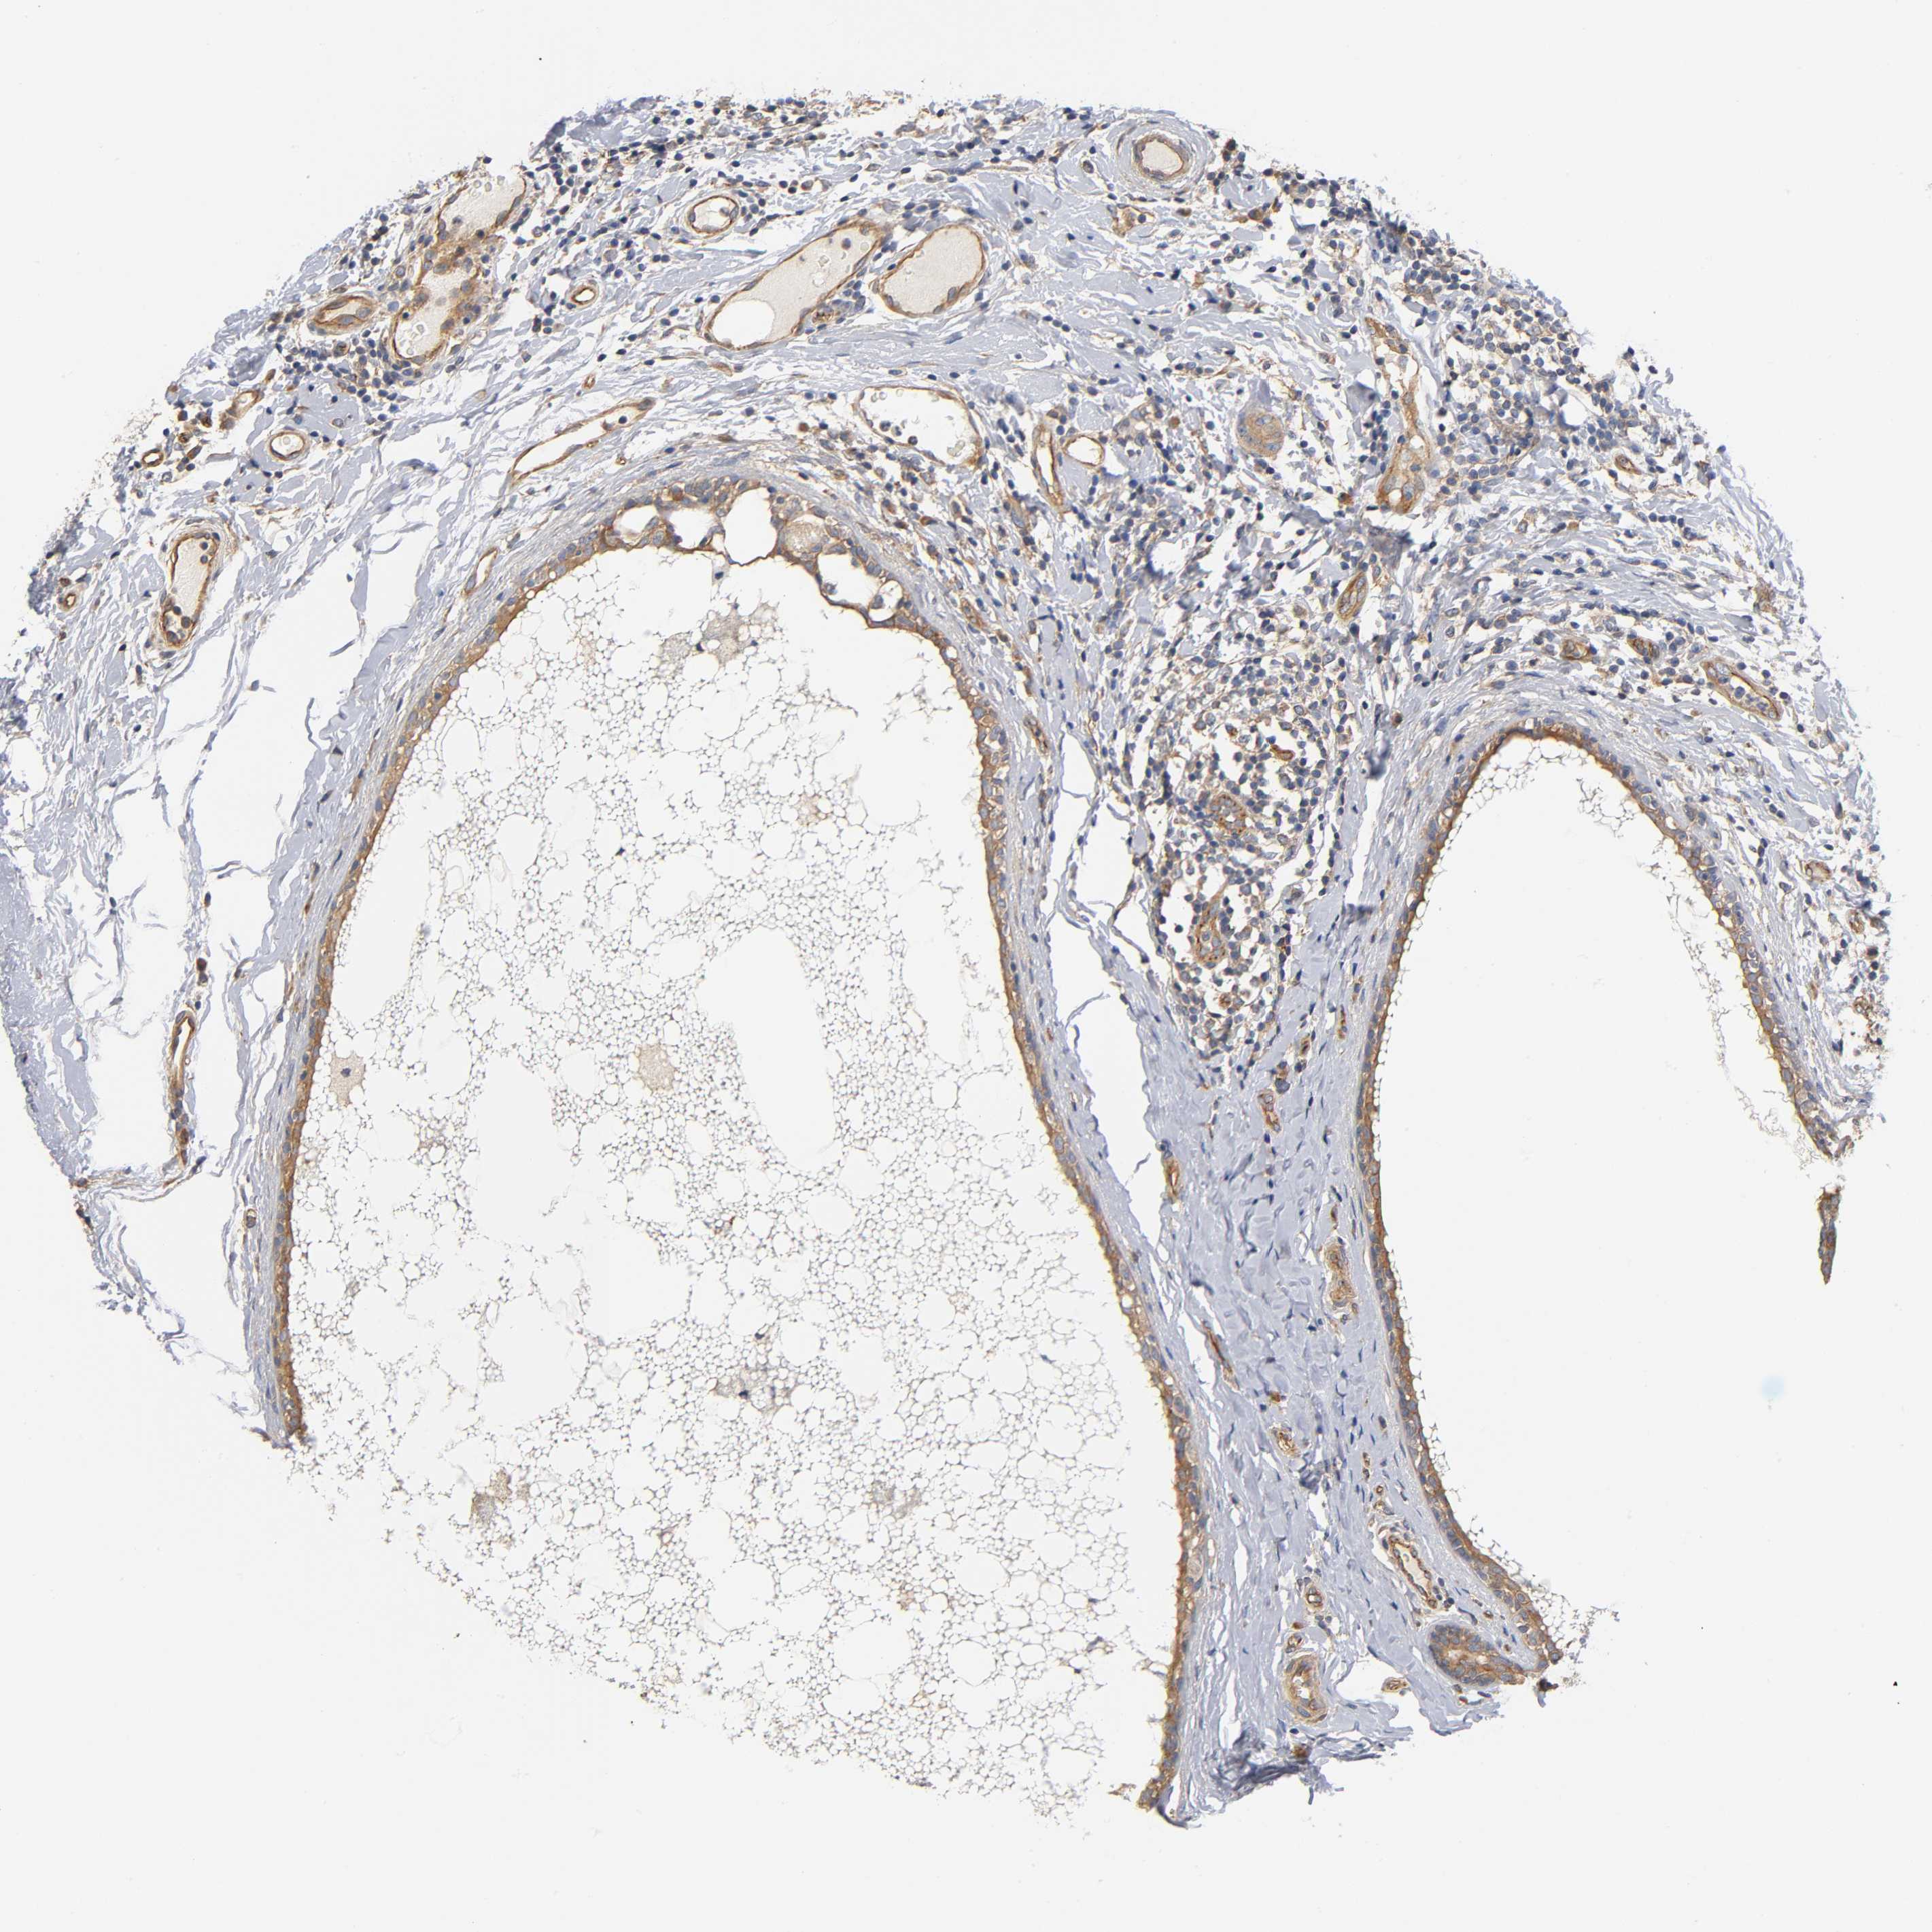

CANCER BREAST CANCER Show tissue menu

Breast cancer

Human cancer